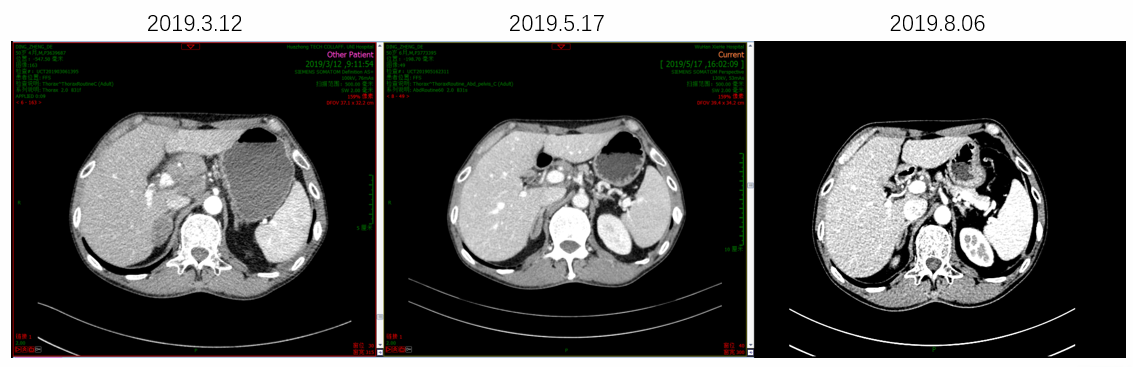

因患者PS评分差,故推荐单药PD-1单抗治疗,患者考虑后选择信迪利单抗。2019年3月20日开始使用信迪利单抗治疗1次,当日出现发热39.3℃,予以退热栓退热治疗后好转。4天后,患者PS评分明显好转,下床活动自如,食欲增强,PS评分由3分改善到1分。2019年4月11日和2019年5月1日分别再使用信迪利单抗治疗各1次。2019年5月17日复查腹部CT,肝脏病灶较前明显缩小,肝门淋巴结较前明显缩小;复查胸部CT,肺部病灶也较前明显缩小。总体疗效评价为PR。多次治疗中外周血EBV-DNA拷贝数检测结果显示,信迪利单抗治疗后EBV-DNA明显降低。

image013.png

图4 信迪利单抗治疗前后肝脏病灶明显缩小

image017.png

图5  信迪利单抗治疗前后肝门淋巴结明显缩小